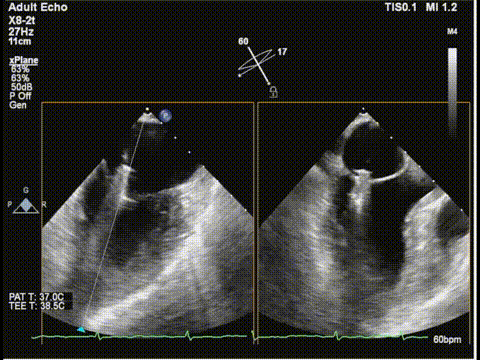

三尖瓣

三尖瓣反流以膈叶脱垂为主,反流主要集中在前叶和膈叶间,从中心区向边缘区的蔓延。后叶又有分了两个叶,分型上属于IIIb型的三尖瓣反流。

三尖瓣胃底界面

三尖瓣胃底界面color